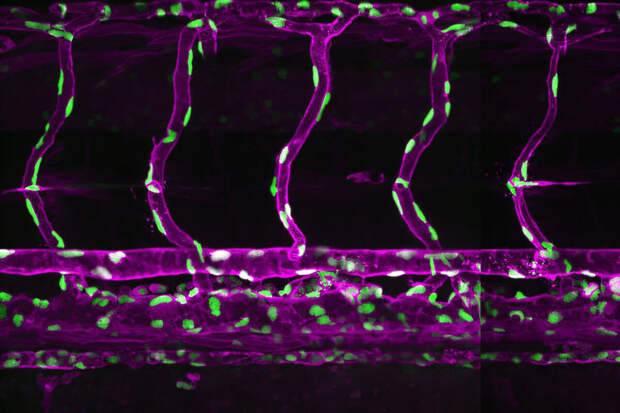

Ru" в пресс-службе научного учреждения.Эпителиальная ткань обладает уникальной способностью к переупаковке — процессу, при котором клетки изменяют форму и положение, сохраняя при этом прочные связи между собой. Механизм обеспечивает быстрое восстановление тканей после повреждений, но при онкологических заболеваниях дает сбой, приводя к бесконтрольному делению клеток и образованию метастазов.

Новая модель, в отличие от существующих аналогов, учитывает изменение формы клеток, химические сигналы между ними и различия в типах тканей. Она основана на усовершенствованной вершинной модели, где клетки представлены как многоугольники, реагирующие на механические и химические воздействия.

Важным результатом исследования стало определение оптимального значения интеркаляции (dint = 0,40), при котором ткань демонстрирует максимально устойчивое поведение, характерное для здорового организма.